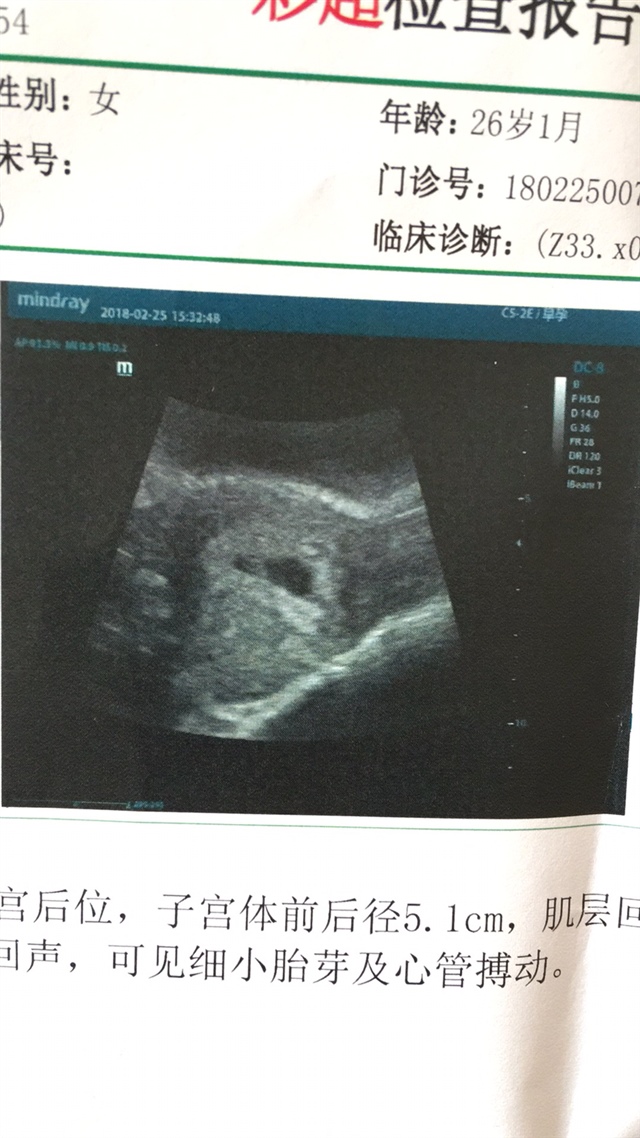

东骏退货组-肖春艳[帖主]:3.0*1.2*2.5